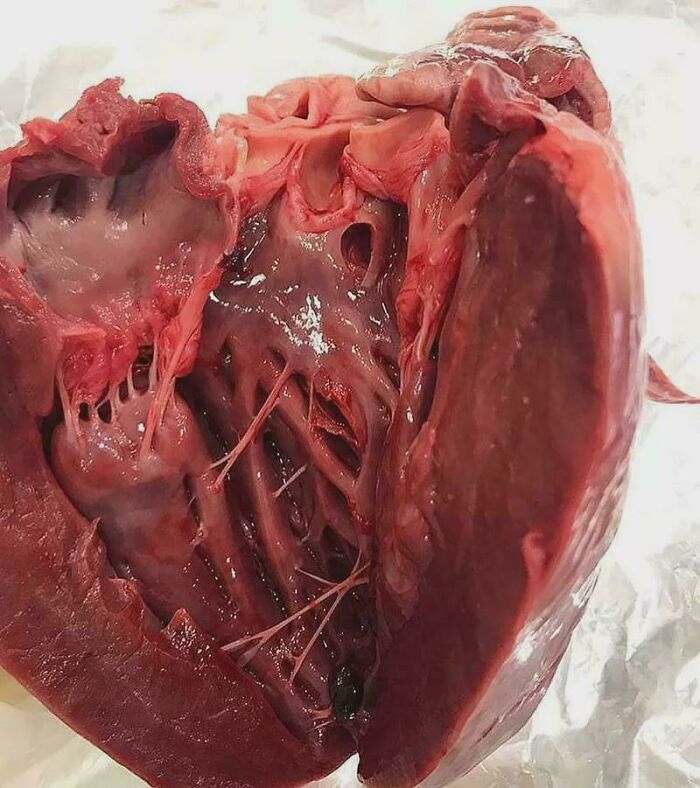

Hypertrophic Cardiomyopathy: Thickening Heart Gets Its Own Close-Up

This heart muscle got big - really big - thickening like a bodybuilder’s biceps. This scary condition mainly hits the ventricles, changing the rhythm and pump of the heart. Athletes might look like this naturally, but this is a different (and not-fun) story.